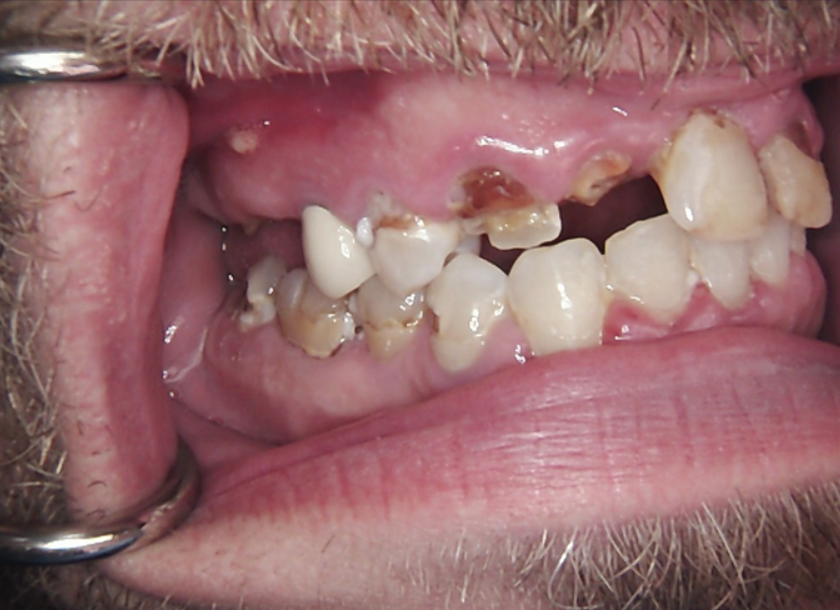

Long-term psychoactive substance use had caused severe xerostomia, contributing to the rapid development of dental caries and decay. The teeth in the upper jaw were non-restorable, and many were already missing. The condition of the lower jaw was slightly better: the anterior teeth were in satisfactory condition, but the posterior teeth were severely decayed and required extraction.

The presented images show the patient’s initial dental condition.